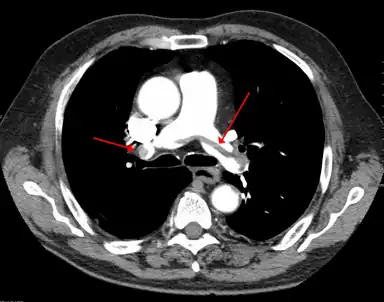

A pulmonary embolism (PE) occurs when a blood clot from a deep vein (a DVT) detaches from a vein (embolizes), travels through the right side of the heart, and becomes lodged as an embolus in a pulmonary artery that supplies deoxygenated blood to the lungs for oxygenation.[28] Up to one-fourth of PE cases are thought to result in sudden death.[12] When not fatal, PE can cause symptoms such as sudden onset shortness of breath or chest pain, coughing up blood (hemoptysis), and fainting (syncope).[29][30] The chest pain can be pleuritic (worsened by deep breaths)[29] and can vary based upon where the embolus is lodged in the lungs. An estimated 30–50% of those with PE have detectable DVT by compression ultrasound.[30]

A CT image with red arrows indicating PE (grey) in the pulmonary arteries (white)

A CT image with red arrows indicating PE (grey) in the pulmonary arteries (white) A case of phlegmasia cerulea dolens in the left leg